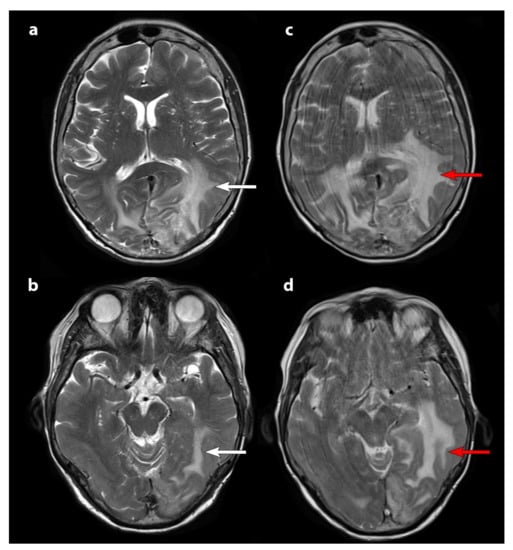

| 1 | 3 | II | 7.4 | 10.6 | PD | 2 months |

| 2 | 3 | II | 26.3 | 29.6 | SD | 10 months |

| 3 | 3 | II | 45 | 29.6 | SD | 17 months |

| 4 | 2 | II | 14.5 | 29.6 | SD | 16 months |

| 5 | 2 | III; II | 12.3 | 29.6 | SD | not reached at 12 months |

| 6 | 3 | II | 16 | 29.6 | SD | not reached at 9 months |

| 7 | 3 | II | 16.8 | 29.6 | SD | N/A * |

| 8 | 3 | II | 15.4 | 29.6 | SD | not reached at 16 months |